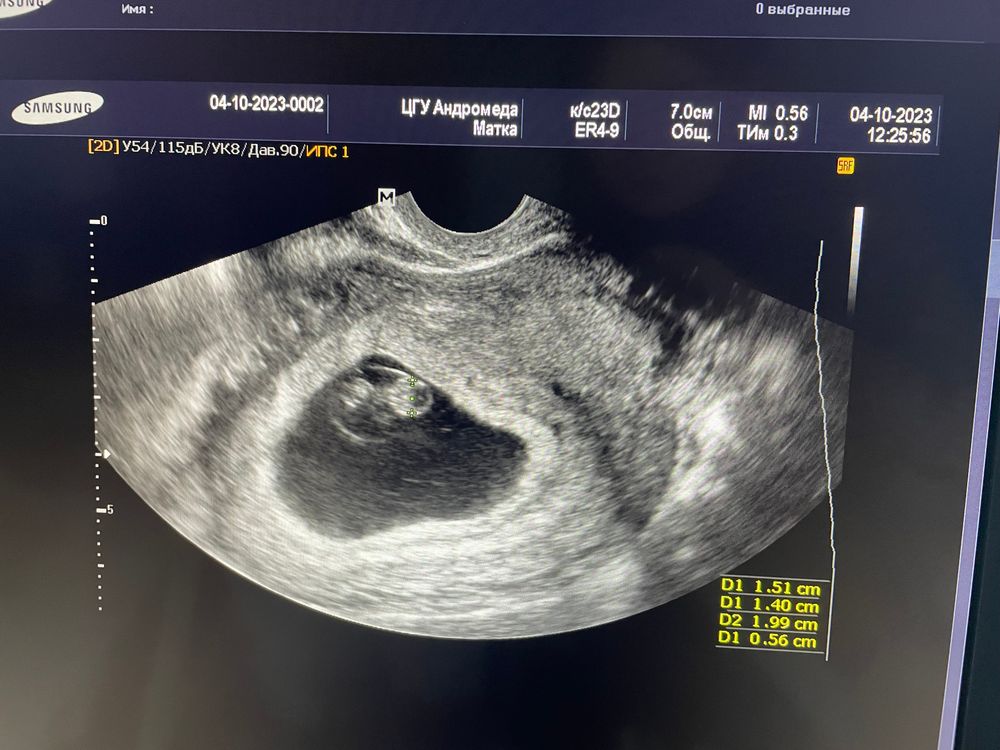

узи 8.1 недель

крошка! ктр 15мм, жм 3мм, жт 22мм, сб 150

незначительно деформировано плодное яйцо при всех остальных показателях в норме :( очень переживаю, прием у врача только завтра. подскажите, у кого так было, какая причина и что было потом?